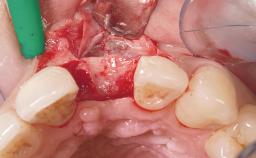

A 33-year-old female patient presented with an upper left central incisor that required extraction after a failed endodontic therapy. The tooth had been traumatized when the patient was a teenager and had undergone several endodontic treatments, including two apicectomy procedures. The patient was in good health and did not smoke. Clinical examination showed that the patient had a high lip line. In full smile, the gingival margins of the upper teeth were visible to the first molars. The gingival margins of central incisors 11 and 21 were only just showing. Examination of tooth 21 confirmed that the tooth was mobile and had hypererupted by 1 mm.

Soft Tissue Grafting Simultaneous

Placement Protocol Immediate implant placement

Socket Integrity Damage to one or more bone walls

Bone Volume Damage to one or more socket walls